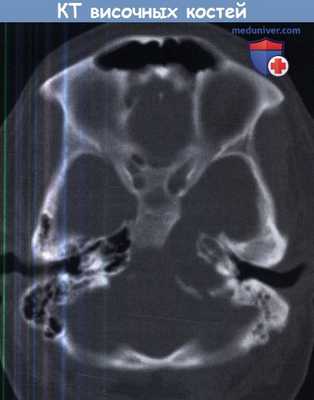

КТ височных костей. Тотальное снижение пневматизации ячеек сосцевидного отростка с обеих сторон. (фото Вишняков В.Н.)